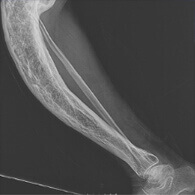

НАСЛІДКИ ТА РИЗИКИ

Деформація кісток

Нестерпний біль

Параліч

Повна втрата дієздатності

За відсутності правильного лікування хворі суглоби дають найважчі ускладнення на весь організм. Щоб уникнути непоправних наслідків у вигляді часткового або повного паралічу приступайте до лікування якомога швидше!